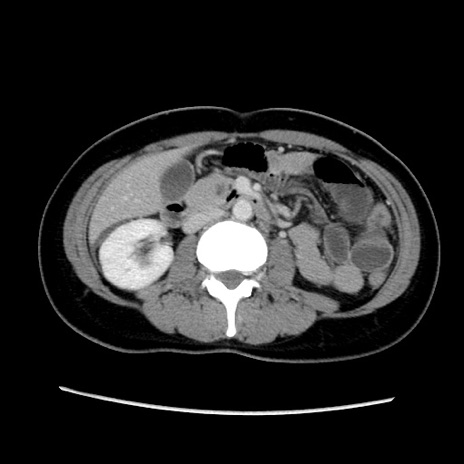

症例39(横断像)

【症例】40歳代女性

【主訴】上下腹部痛

【現病歴】2日目から下腹部痛あり。夜間は痛みで眠れなかった。昨日より上腹部痛と下痢が出現。臥位で痛みは軽快したため、休んでいた。本日になって臥位でも立位でも痛みが強くなってきたため救急要請。

【既往歴】子宮内膜症

【身体所見】部:平坦・軟、左上下腹部に圧痛あり、反跳痛あり。

【データ】WBC 21800、CRP 26.78